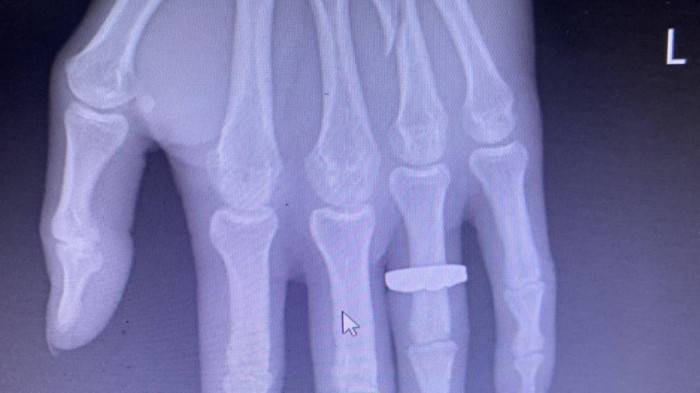

Bệnh án của Bệnh viện Đa khoa Bãi Cháy ghi nhận, anh Sáng bị gãy xương áp út bên tay trái, đa chấn thương đầu, mặt. Hiện ngoài vùng mắt trái còn thâm tím, đầu anh Sáng phía bên trái còn rõ vết rách khoảng 2cm mới liền, vùng vai, gáy vẫn bị sưng, đau.

Vết gãy trên ngón tay áp út của anh Sáng do Bệnh viện Đa khoa Bãi Cháy chụp